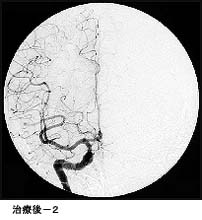

脳動静脈奇形に対する液体塞栓物質を用いた治療

治療により異常血管は閉塞されました。